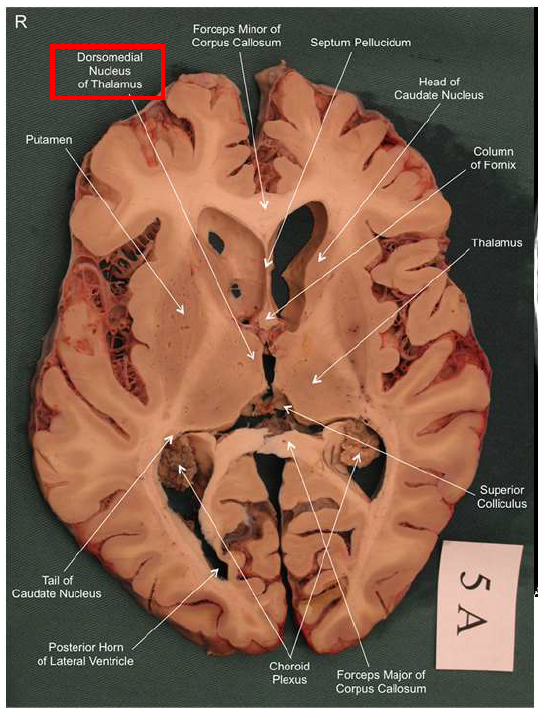

What is the fornix of the hippocampus?

Hippocampus output pathway (C-shaped)

Connects hippocampus to hypothalamus/mamillary bodies

Carries information to and from hippocampus

Important for memory consolidation and retrieval

How does the hippocampus form memories?

Association areas activate the hippocampus, which reverberates in the Papez circuit until information is stored permanently

Hippocampus → fornix → mamillary bodies → anterior thalamic nucleus → cingulate cortex → hypothalamus